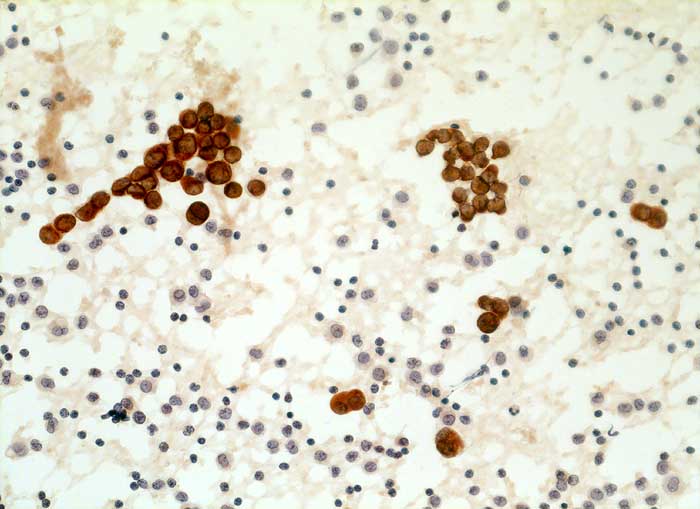

l/ Panzytokeratin (CK22/Lu-5)

Panzytokeratin (CK22/Lu-5)

Anfärbung:

Zytoplasma positiv.

Reaktion in Neoplasien:

Die meisten Karzinome und vereinzelte Sarkome reagieren positiv mit diesen Panzytokeratinen. CK22 ist etwas sensitiver und spezifischer als Lu-5. Entdifferenzierte oder sarkomatoide Karzinome können die Positivität für Zytokeratine verlieren.